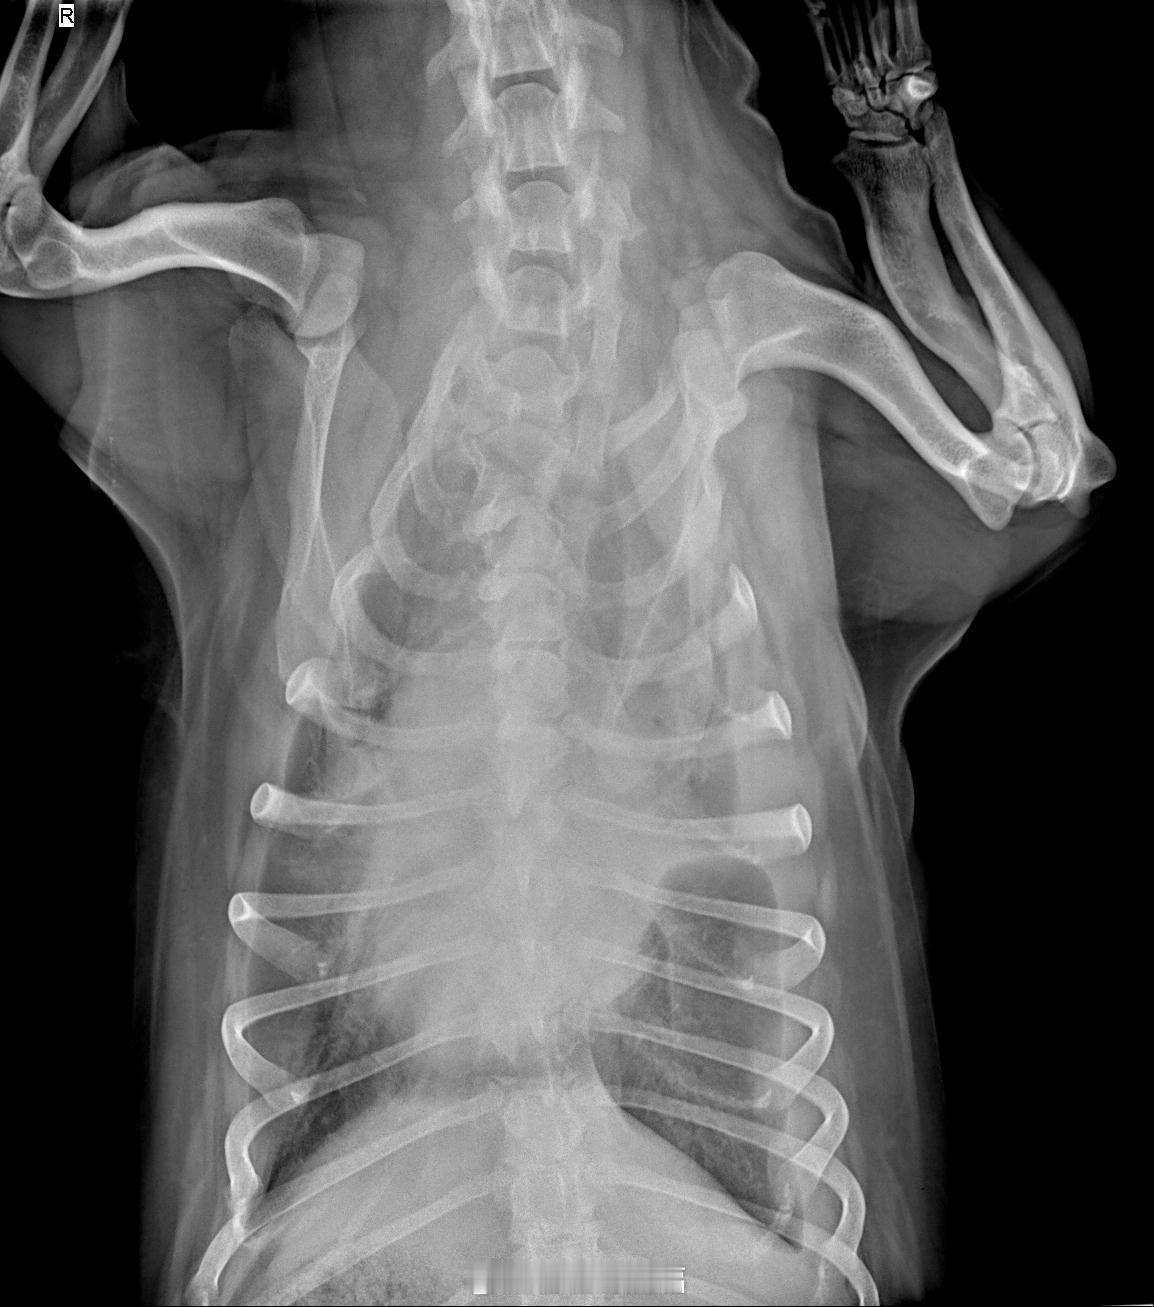

怀疑是间质细胞瘤,恶性特征明显